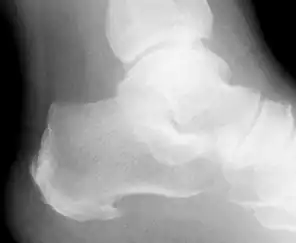

La fascitis plantar ha sido relacionada frecuentemente con la existencia de espolón calcáneo, un hallazgo radiológico consistente en una exostosis del calcáneo, reacción perióstica al aumento de tracción de la musculatura plantar medial del pie; aunque no debe considerarse como patognomónico de esta enfermedad, dado que la fascia plantar se inserta por encima del espolón y no como prolongación del mismo.